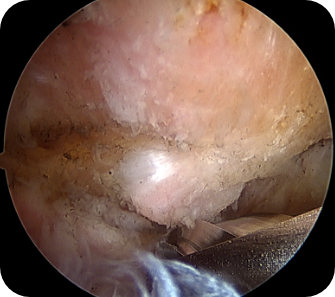

회전근개 질환, 오십견, 어깨 탈구 등 어깨 질환은 어깨의 통증과 고통을 야기합니다. 어깨 관절내시경 수술은 관절 질환이 의심되는 부위를 1cm 미만으로 최소절개한 뒤, 내시경 카메라와 수술 기구를 관절 내부에 삽입해 질환을 진단하고 치료하는 수술입니다. 화면을 통해 병변 부위를 직접 확인할 수 있어 손상 정도에 따라 파열된 힘줄을 봉합하거나 염증을 제거할 수 있습니다. CT나 MRI 등의 진단으로 잘 보이지 않던 곳까지 내시경을 삽입할 수 있어 적용 범위가 점점 넓어지고 있는 추세입니다.

- 오십견의 치료에 효과적입니다.